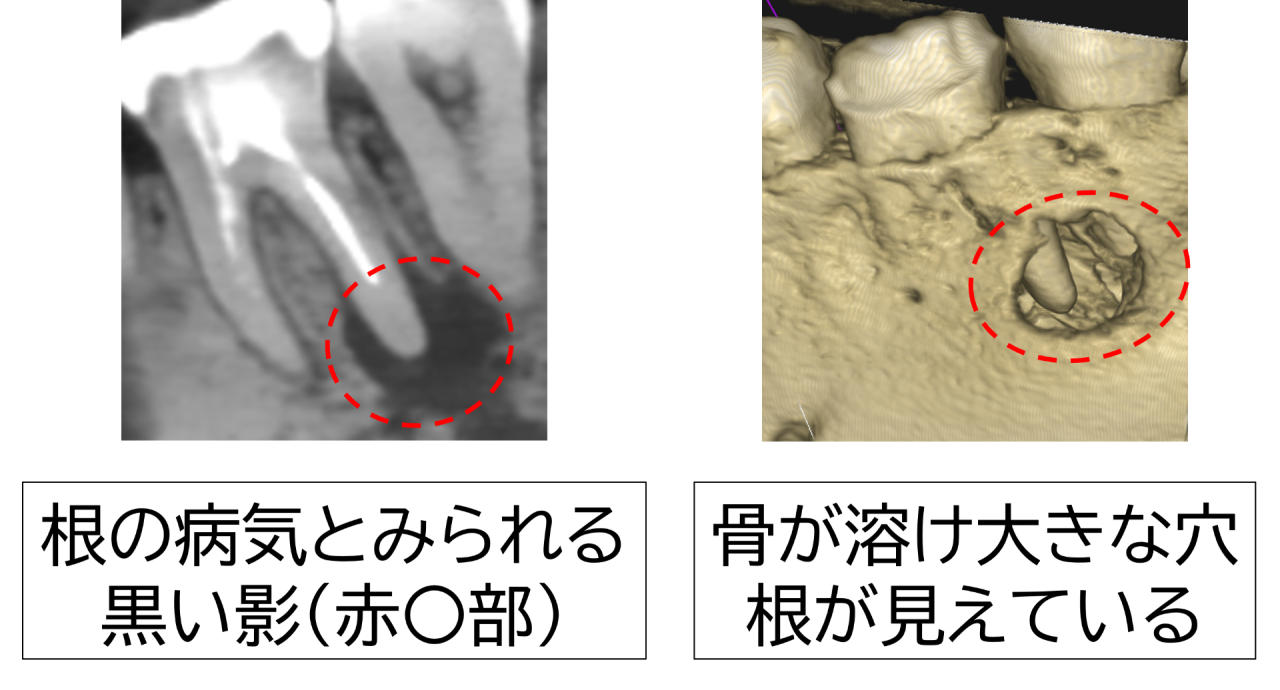

レントゲン(CT)撮影で詳細に確認しました。根の先に大きな病気とみられる透過像(黒い影)が認められ、骨が広い範囲で溶けてしまっている状態でした。診断は「慢性根尖性歯周炎」。

原因は神経の取り残しと考えられました。取り残された神経が死んで腐敗し、細菌が増殖して根の病気を作ったのです。